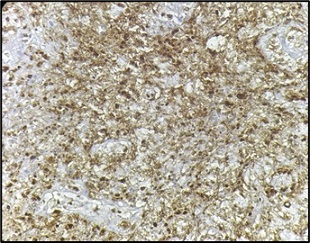

Figure 9. Tumor Cells are Diffuse and Strong Positive for CD45 (100X).

Figure 10. Tumor Cells Show Diffuse Cytoplasmic Positivity for CD20 (100X).

On the basis of histopathological features, differentials considered were metaplastic carcinoma and lymphoma. Immunohistochemistry was positive for CD45 (Figure 9), CD 19, CD20 (Figure 10), MUM-1 (Figure 11), BCL2 (Figure 12) and negative for ER, PR, Her2neu, P63, CK5/6, vimentin, CD3, CD5, CD10 and BCL6.